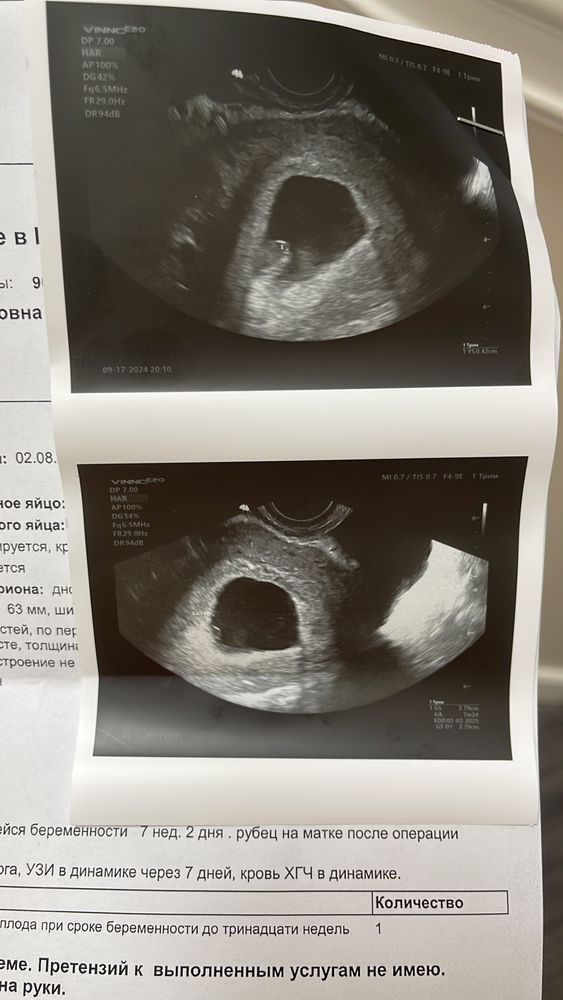

Мама мальчика (13 лет) Москва

Алена, Изображение

Виктория , на 1 и 2 узи желточный мешок визуализировался. На последнем ничего не сказали и не описали

Виктория , строение эмбриона не визуализируется отметили и кровотока нет